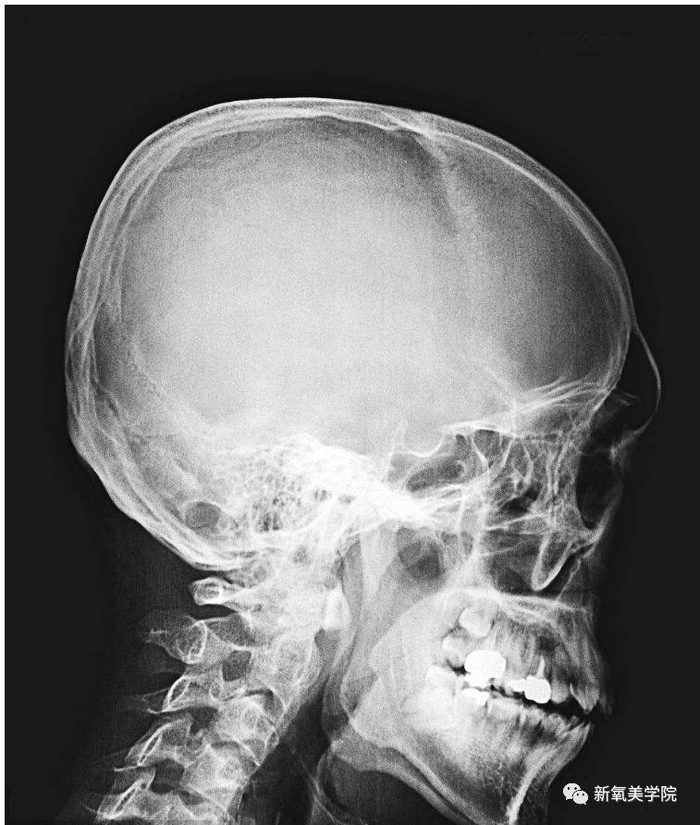

但是美术方法只是用来了解自己,在自己真正决定要正颌手术的时候,都是需要去照X光片的。

将一个人耳孔(下图数字25,标三角的位置)和眶下孔(下图数字35)划直线,再垂直方向划竖线,和牙龈形成的角度不超过30度,就是比较显年轻可爱的三分龅。